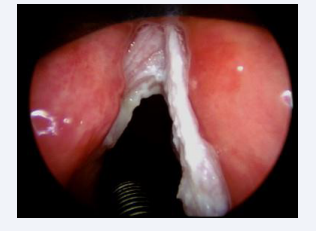

This prevalence is justified due to the surgeon’s special attention during the trans-operative period, and the following aspects were observed: the leukoplakia may be microscopic, it may be located throughout the glottis, especially at the vocal fold level, it may be associated to the initial surgical lesion, it may be contralateral to it, it may be located in the epithelium of this lesion or it may also be subglottic. Intraoperative staging with microscopy, palpation maneuvers and the use of rigid endoscopes angled at 30, 70 and 120 degrees favor the detection of leukoplastic lesions [Figures 2-5].

Leukoplakia with variation in location and quantity

Figure 2: Leukoplakia with variation in location and quantity